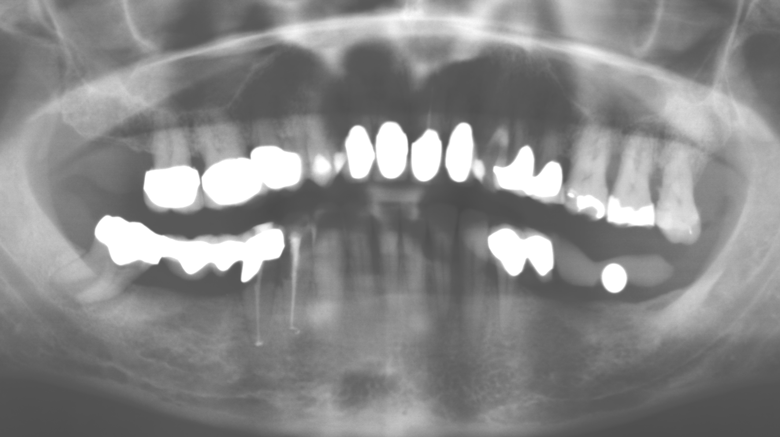

A 52-year-old patient presented in our clinic for the first time in 2004 following tooth loss in the third quadrant, expressing a desire for a new prosthetic restoration. Periodontal and radiological diagnostics revealed the need for extensive periodontological treatment. In addition, teeth 48, 28 and 27 were attributed a very poor prognosis and were subsequently extracted (Fig. 1). Following the successfully completed, systematic periodontological treatment, a fixed dental implant was inserted with the introduction of five implants in tooth regions 35, 36, 37, 46 and 47. Prosthetic treatment of the natural teeth was effected with veneered zirconium dioxide ceramic crowns; the implants were composed of two-piece, individual zirconium dioxide abutments and similarly veneered crowns made of a zirconium dioxide ceramic (Cercon base colored, Dentsply Sirona Lab). Definitive insertion of the prosthetic restoration occurred in 2005.

Due to the presence of periodontal disease, SPT was performed every three months in the first years following the insertion. The patient demonstrated a high degree of motivation and good compliance. The pocket depths recorded annually revealed a stable periodontal situation with a BOP index of below five per cent. On the basis of the stable periodontal situation and good cooperation on the patient’s part, the recall interval was extended to every six months as of the sixth year of the prosthetic function phase. Following the change in the recall interval, the respective annual documentation of the periodontal status continued to reveal a stable periodontal situation with no increase in the pocket depths and a BOP index below five per cent (Fig. 2a and b).